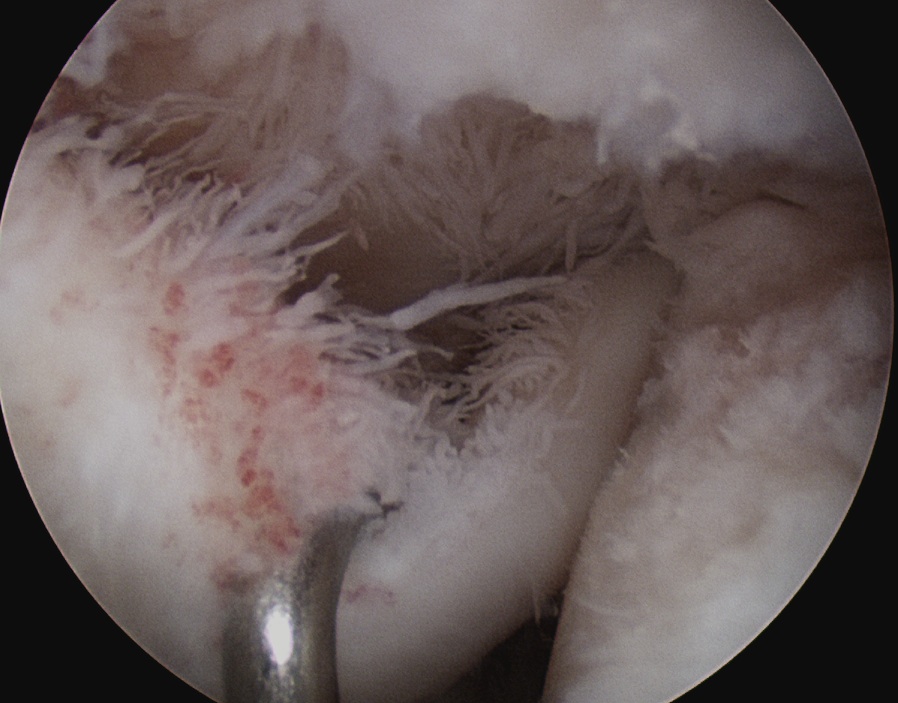

Arthroscopy

Glenoid cartilage wear

Humeral head cartilage wear